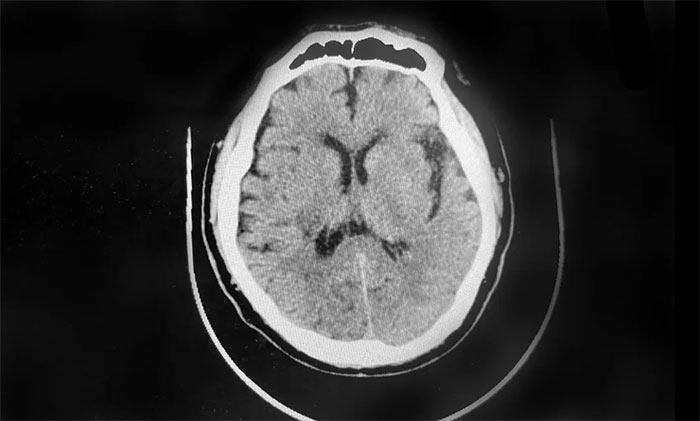

▲ 经治疗,血肿逐渐吸收